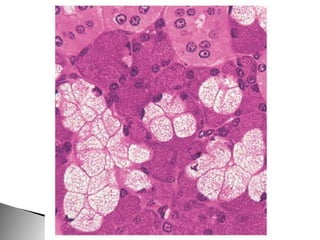

Este documento presenta imágenes microscópicas de diferentes tipos de tejidos y estructuras celulares teñidas con varios métodos histológicos. Incluye fotografías que muestran fibras de colágeno, elásticas y reticulares en diversos órganos, así como membranas basales y células especializadas de órganos como riñones, glándulas mamarias y próstata. El propósito es demostrar la aplicación de técnicas histológicas para visualizar componentes celulares y tej